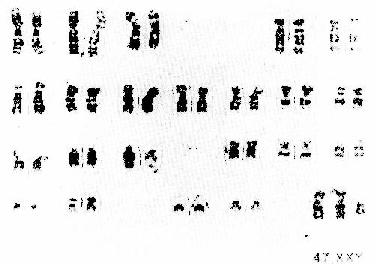

(6)Klinefelter综合征:又称先天性睾丸发育不全症。典型的核型是47,XXY。表型特征有睾丸发育不全。身材修长,乃足跟至趾骨间的距离增长所致。男子乳腺发育、阴毛呈女性型分布,阴茎及睾丸均小。严重者伴有智力迟钝、隐睾及尿道下裂等(图6-7)。

图6-7 Klinefelter综合征的核型47,XXY

由于增加一条X染色体,影响睾丸发育